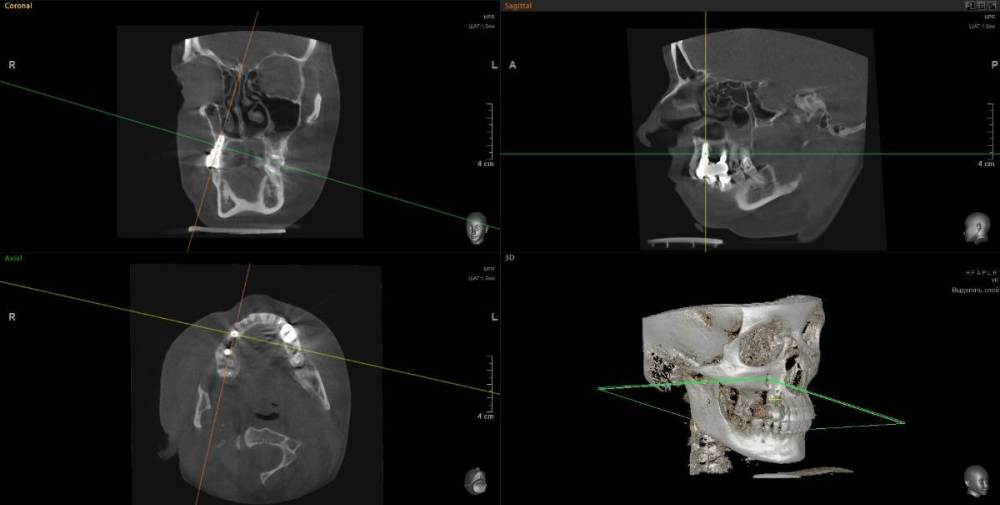

1. Сильное воспаление верхнего зуба привело к воспалению пазухи носа 2. Импланты 2 года (общая ст-ть 200 тыс.), тоже воспаление, рекомендовано удалить

1. Из-за сильного воспаления верхнего зуба костная кость растворилась и дошло до пазух носа. Зуб рекомендуют удалить

2. Импланты установила 2 года назад, в итоге заплачено было 200 тыс. с учетом циркониевых коронок. На КТ обнаружилось сильное воспаление, как следствие растворилась костная ткань импланты, доктор сказал уже не спасти.

Буду очень признательна за консультацию - действительно ли нужно удалять зуб и импланты? КТ во вложении

IMHO. Зуб 18 стоит удалить, зуб 17 стоит полечить. Имплантат в позиции 16, похоже, придётся удалить, имплантат в позиции 14, на мой взгляд, вне опасности.